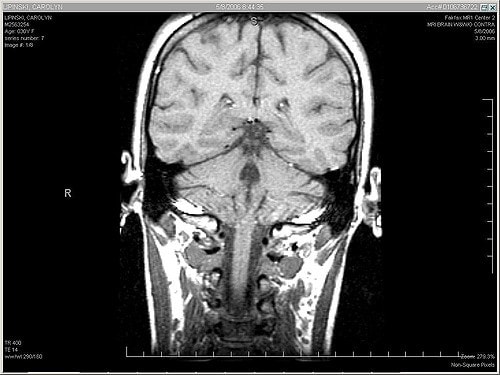

- Компьютерная томография (КТ) и магнитно-резонансная томография (МРТ);

- Магнитно-резонансная томография мозга позволяет выявить инфаркт, инсульт, рассеянный склероз и аденому гипофиза.